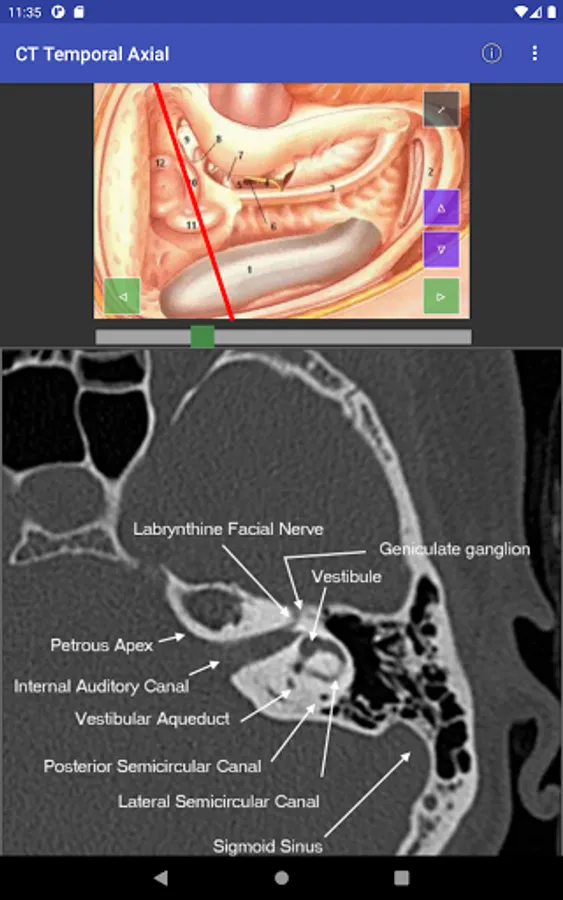

For easy of understanding CT scan anatomy, the content is correlated in two planes, with one serving as a reference. Hence it is much easier to understand the anatomy as we face in the clinical situation. Both the planes can be individually scrolled, so depth is easier to understand.